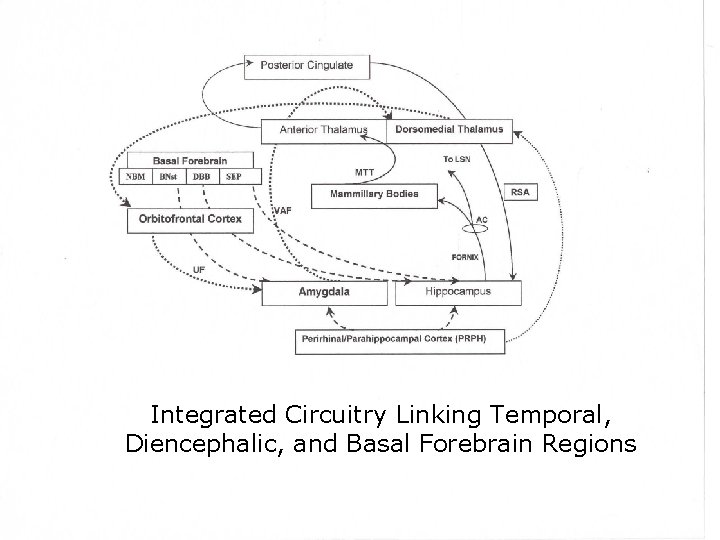

Integrated Circuitry Linking Temporal, Diencephalic, and Basal Forebrain Regions

Two Limbic Circuits Anterior Thalamus Cingulate Gyrus Dorsomedial Thalamus Mamillothalamic Tract Mammilary Bodies Fornix Hippocampus Medial (Papez) Orbitofrontal Amygdalofugal pathways Uncus Amygdala Lateral

Two Limbic Circuits and the Two-system theory of amnesia Anterior Thalamus Cingulate Gyrus Dorsomedial Thalamus Mamillothalamic Tract Mammilary Bodies Orbitofrontal Amygdalofugal pathways Fornix Uncus Hippocampus Amygdala PRPH Medial (Papez) Lateral

Two Limbic Circuits and the Two-system theory of amnesia Anterior Thalamus Cingulate Gyrus Dorsomedial Thalamus Mamillothalamic Tract Mammilary Bodies Fornix Hippocampus Medial (Papez) Orbitofrontal Amygdalofugal pathways Uncus Amygdala Lateral

Two Limbic Circuits Anterior Thalamus Cingulate Gyrus Dorsomedial Thalamus Mamillothalamic Tract Mammilary Bodies Fornix Hippocampus Medial (Papez) Orbitofrontal Amygdalofugal pathways Uncus Amygdala Lateral

Two Limbic Circuits Anterior Thalamus Cingulate Gyrus Dorsomedial Thalamus Mamillothalamic Tract Mammilary Bodies Fornix Hippocampus Medial (Papez) Orbitofrontal Amygdalofugal pathways Uncus Amygdala Lateral Bauer, Grande, & Valenstein, 2003

Key Points • Extended memory system including hippocampus, amygdala, and basal forebrain • We (basically) understand anatomy, now we need to understand computation • Notion of distinct subtypes of amnesia generally less favorable now than 10 years ago • Certain structures are ‘wired’ for associational processing; these structures are reciprocally connected to cortical processors